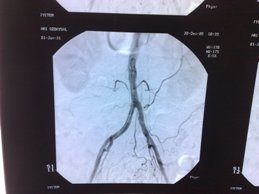

- Klasik anjiografi (Röntgen ışınları olan X-Ray ile)

Anjioplasti genellikle daralmış ve bazen de tamamen tıkanmış arterlerin (atardamar) genişletilmesi veya açılması için kullanılan, cerrahi olmayan bir işlemdir. Bu işlem ile damarlara balon ile genişletme işlemleri yapılabilmekte ve kalıcı stentler konulabilmektedir.